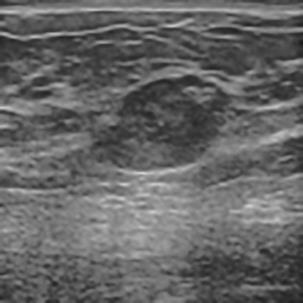

乳腺癌是全球女性最常见的恶性肿瘤之一,准确的病变分割对于乳腺癌的早期诊断与治疗具有重要意义。然而,由于病变形态的多样性以及超声成像机制的复杂性,现有基于深度学习的乳腺超声图像病变分割方法在分割准确性方面仍面临巨大挑战。为进一步提升乳腺超声图像中病变区域的分割精度,该文基于经典U-Net架构,提出了一种新型乳腺超声图像病变分割网络(CWSASKM-BBAM-Net)。首先,在网络中引入逐通道空间自适应选择核卷积模块(CWSASKM),根据不同通道的语义特征为每个空间位置自适应选择感受野大小,以增强多尺度信息的建模能力;然后,引入双向边界感知机制(BBAM),通过融合正向与反向注意力,对目标显著区域及其边界进行协同建模,同时逐步提升对非显著区域与病变区域的区分能力,以进一步强化边界信息的表达;最后,在3组公开乳腺超声图像数据集(BUSI、UDIAT和STU)上开展分割实验。结果表明:该方法在数据集BUSI上的杰卡德指数、精确率、召回率和Dice相似系数分别为71.97%、82.85%、81.40%和80.44%,较次优方法分别提升1.69、1.05、1.28和1.84个百分点;在数据集UDIAT上,这4项指标分别达到78.14%、88.31%、86.73%和86.10%,较次优方法分别提升了2.75、2.04、0.56和2.01个百分点;在外部数据集STU上,该方法也取得了优于其他方法的整体表现。实验结果表明,CWSASKM-BBAM-Net在乳腺超声图像分割任务中展现出更优的整体性能。